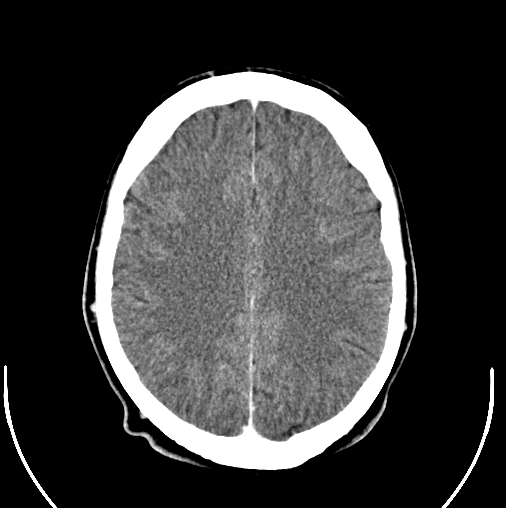

Anemia May Lead to Increased Risk for Dementia

While there is still no test to determine if someone has dementia, a new study finds that older adults with anemia are at an increased risk for dementia.